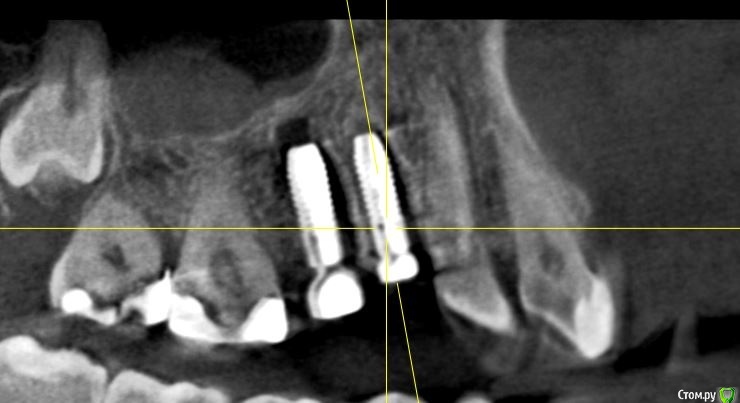

Irouil Опубликовано 29 сентября, 2020 Поделиться Опубликовано 29 сентября, 2020 Итак, друзья, зайдём с козырей? 1.4, 1.5 зубы, удаление + одномоментно винты, прошел месяц, ортопед посмотрел снимки и сказал, что их надо бы удалить. Если удалять, то сейчас, конечно, но у меня есть определённые сомнения))) Ну, или проще говоря, я грешу на коллегу, что он просто о..ел Развейте, пожалуйста, снимите грех с души моей Ссылка на комментарий

Доктор Хаус Опубликовано 29 сентября, 2020 Поделиться Опубликовано 29 сентября, 2020 А между ними 3 мм есть? Вестибулярно не завалены? На первый взгляд все ок. А фото есть? Ссылка на комментарий

Irouil Опубликовано 29 сентября, 2020 Автор Поделиться Опубликовано 29 сентября, 2020 (изменено) По ориентации оси импланта на бугор антагониста я бы делал выводы о вестибулярном завале Не замерял сколько между ними, ну на глаз где-то 3 и есть Фото с винтами во рту нет, к сожалению, но ортопед рот тоже не смотрел, вердикт по снимкам Изменено 29 сентября, 2020 пользователем Irouil Ссылка на комментарий

Irouil Опубликовано 29 сентября, 2020 Автор Поделиться Опубликовано 29 сентября, 2020 Если включать перфекциониста, то есть незначительный завал, но это ж все нормально ортопедируется.Тут надо делить теорию и практику, на мой взгляд. Перкпучивать в человеке винты потому, что врач не хочет выключать перфекциониста - это не медицина, а IT или инженерия. С точки зрения практики А если говорить теоретически, то просмотрите на первый и последний предоставленные срезы: от зубов до винтов и между винтами минимально необходимые расстояния (замечу, что работа без шаблона), они между собой параллельны. Сдвигать корпусно 1.5 некуда - там вестибуло-медиальный корень 1.6 вестибулярно и дистально, а если убирать вестибулярный наклон - платформа выведет за пределы небной кортикалки. Если же двигать его корпусно вестибуло-медиально (чтобы не приближаясь к корню освободить пространство для небной ротации), то абсолютно идентичное движение должен совершить 1.4 - ровно в сторону корня 1.3. Получается, что единственное, что можно было бы подправить ТЕОРЕТИЧЕСКИ - немного сгладить медиальный наклон, но, опять таки, рискуя либо сближением с корнем 1.6 в пришеечной области, либо, что ещё хуже на мой взгляд, сближением с корнем депульпированного 1.3 в апикальной части. Так что это ещё тот вопрос - где и кто включает перфекциониста. На мой взгляд Ссылка на комментарий

Irouil Опубликовано 30 сентября, 2020 Автор Поделиться Опубликовано 30 сентября, 2020 А как он обосновал что нужно убирать винты? Слишком небно импланты, слишком сильный медиальный завал, слишком близко зубы Ссылка на комментарий

Дмитрий Л. Опубликовано 30 сентября, 2020 Поделиться Опубликовано 30 сентября, 2020 Вы как-то в дебри залезли. По-моему ортопеда просто смутил рисунок лунки) Что касается наклона: с такой ангуляцией нагрузка на винт действительно будет нерациональной, но всё не настолько плохо, чтобы проводить реимплантацию. Ссылка на комментарий